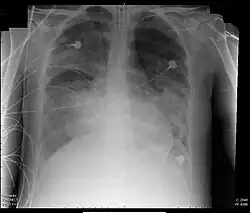

- beidseitige Infiltrate in posterior-anteriorer Röntgen-Thoraxaufnahme

- Radiologie: Beidseitige Infiltrate im Röntgenbild der Lunge oder in der Computertomographie ohne andere sinnvolle Erklärung,

- diffuse röntgenologische Infiltration